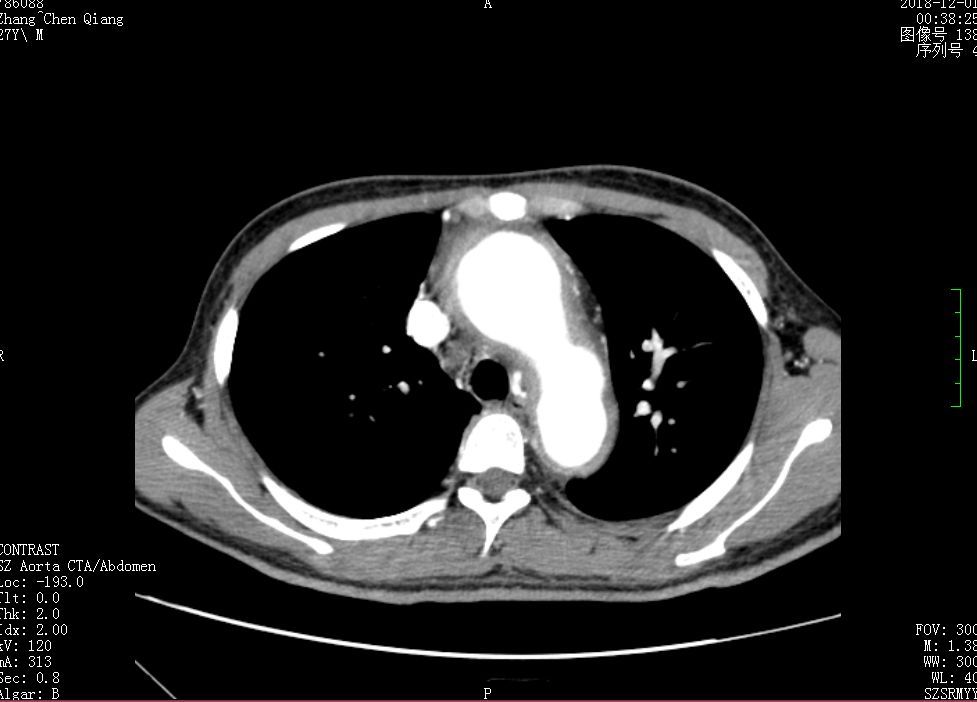

2018年9月,51岁的陈女士(化名)无明显诱因出现咳嗽伴左侧胸痛,在当地医院就诊,被当诊断为为肺栓塞。

当地医院为陈女士行肺动脉造影术+肺动脉溶栓术,当时造影显示左陈女士右肺动脉主干见大量血栓,左肺动脉主干血栓几乎填满管腔!

然而,陈女士在外院经过多次介入下局部溶栓、抽栓治疗,效果却依然不理想。为了进一步治疗,陈女士转到了深圳市人民医院呼吸内科。

此时,陈女士已呼吸衰竭,重度肺动脉高压,随时面临猝死的危险。考虑到陈女士的病情,呼吸内科及时组织两次全院会诊,并联系多学科团队联合救治。

心外科郑奇军主任医师根据患者病史、辅助检查及诊疗经过,考虑陈女士可能是肺血管肿瘤,有手术指证,建议尽早在体外循环下行肺动脉肿瘤摘除术+肺动脉内膜剥脱术。